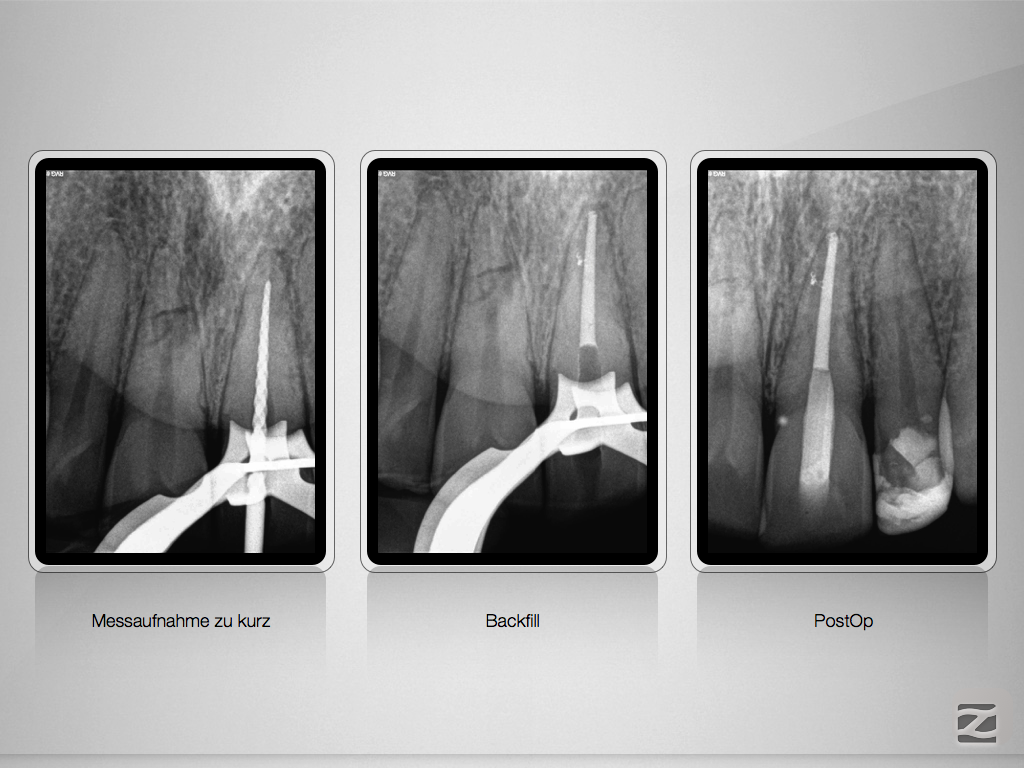

Die Tücke der Endometrie …